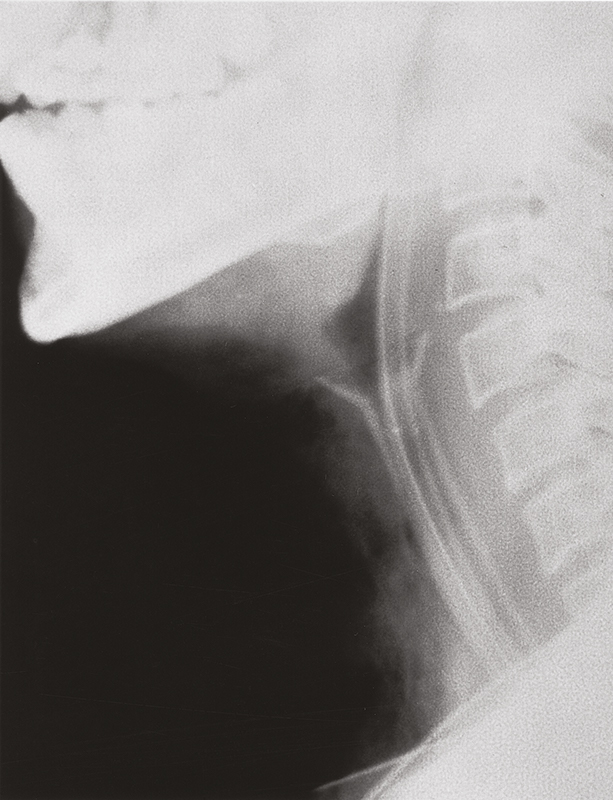

Montgomery Speichel-Bypass-Tubus

Der dauernde Kontakt des durch Operation, Infektion oder Strahlentherapie verletzten Gewebes mit dem Speichel ist der Hauptgrund, der den Heilungsprozess und den Fistelverschluss behindert.

Der Montgomery Speichel-Bypass-Tubus lenkt den Speichel in den distalen Ösophagus und erleichtert einen Spontanverschluss der Fistel oder eine für Reparaturmaßnahmen ausreichende Erholung des Gewebes.